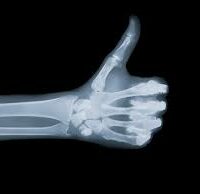

Nos Examens Radiographie IRM Ostéodensitométrie Scanner Echographie Mammographie Radiologie dentaire Radiologie interventionnelle